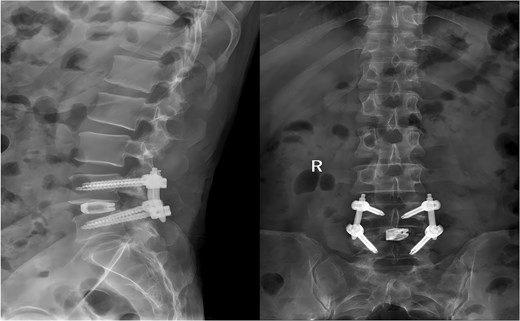

Following the surgery, the patient remained in stable condition with no reported discomfort. Postoperative radiographs verified complete extraction of the guidewire, with no residual fragments observed at the fracture site (Fig. 6). The patient experienced an uneventful recovery, and subsequent follow-up evaluations demonstrated satisfactory outcomes.

Postoperative anteroposterior and lateral radiographs of the lumbar spine.